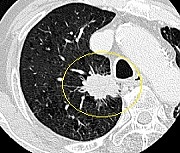

腺がんは初期の病変ではすりガラス状陰影(Ground Glass Attenuation : GGA)であることが多く、胸部レントゲン検査では発見が非常に難しく、高分解能CT(HRCT)が有用です(左図)。